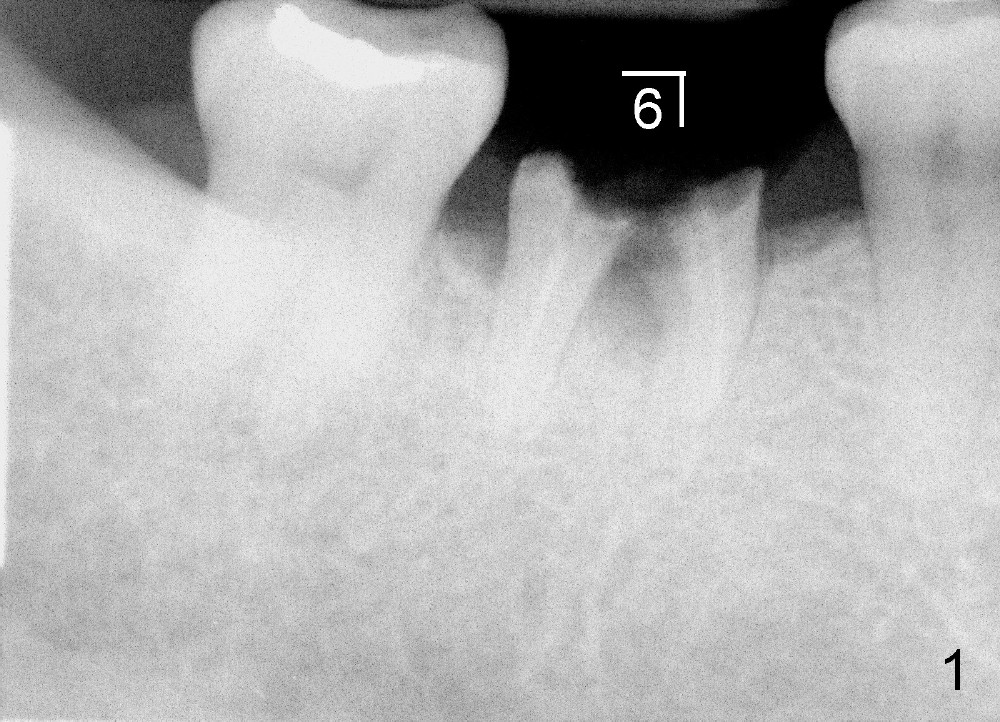

A sixty-year-old lady fractured the crown of the lower right first molar (Fig.1). The residual roots were sectioned (Fig.2 between arrowheads) and removed. The septum (Fig.3 *) is round on the top between mesial and distal sockets (1,2). Thin osteotomes (bone scalpel, bone blade; Fig.4: T) were used to section the septum mesiodistally. Fig.5 shows the sectioned septum, which makes it easy to insert round tapered osteotomes (Fig.5 inset green; Fig.6 R) without slipping either into the mesial or distal socket.